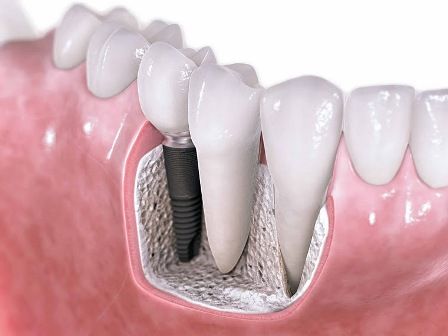

İMPLANT NEDİR? İmplantlar, diş kökü şeklinde titanyumdan hazırlanmış, çene kemiğine küçük bir operasyon ile yerleştirilen suni diş kökleridir. Titanyum doku dostu bir malzemedir. Kemik ile özel bir bağ oluşturarak yerleştirildiği yere, hücresel olarak tutunur. Bu tutunma tamamlandığında (2-6 ay) üst yapı dediğimiz protezi hazırlama işlemine geçilir. Günümüzde implantlar tartışmasız olarak doğal dişe en iyi alternatiftir.

İmplantların Fonksiyonu Nedir? İmplant çene kemiğinize kaynadığından dolayı, yapay dişler için sabit destek sağlarlar. İmplantlara takılan protez ve köprüler, ağzınızın içinde kaymazlar – bu, yemek yemek ve konuşmak için gereklidir. Bu sabit destek , protez ve köprülerin yanı sıra implantlar üzerine yerleştirilen kuronların, geleneksel köprü veya protezlere göre daha doğal hissedilmesini de sağlar.

Diş kayıplarının ya da meydana gelen travmaların sonucunda fizyolojik olarak oluşan kemik erimeleri, çene kemiğinin seviyesinin ve hacminin azalmasına neden olmaktadır. Bu durum, uygulanacak protezin işlevini tam olarak yerine getirebilmesine engeldir. Bunun sonucunda da çiğneme ve konuşmada problemlerin çıkması kaçınılmaz olur.